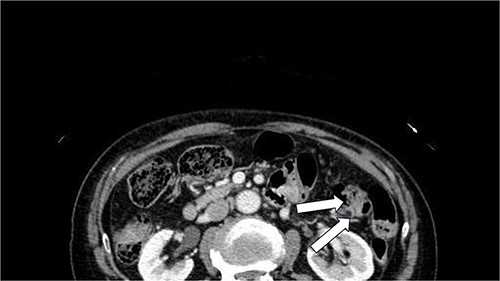

Swelling and tenderness were observed in the left lumbar back area. Abdominal contrast-enhanced CT showed the herniation of the retroperitoneal fat tissue into the abdominal wall was observed dorsally to the left kidney (Fig. 1). Surgery was performed because the pain persisted and there was a possibility of organ incarceration in the future. We used the laparoscopic system to perform the operation. The patient was positioned in the right lateral decubitus position under general anesthesia. A camera was inserted at the umbilicus, and 5 mm ports were placed in the epigastric region and left lower abdomen. The omentum and descending colon were adhered to the abdominal wall and were dissected. The descending colon was dissected laterally along the white line, and the dorsal side of the Gerota’s fascia was dissected. A 3 cm × 2 cm hernia orifice, bordered by the 12th rib lower edge, internal oblique muscle, serratus posterior inferior muscle, and quadratus lumborum muscle, was identified (Fig. 2). Part of the fatty tissue, including Gerota's fascia, was herniated, and it was resected as much as possible. A BARD Ventralight ST 10.2 × 15.2 cm mesh was placed, and it was fixed to the ribs and muscles using the double crown method with AbsorbaTack (Fig. 3). The operative time was 109 minute, with little blood loss. The patient discharged on postoperative Day 2 without postoperative complications. One year has passed since the surgery, and there have been no recurrence of the hernia, neuropathic pain.

Abdominal contrast-enhanced CT showed the herniation of the retroperitoneal fat tissue into the abdominal wall was observed dorsally to the left kidney(arrow).